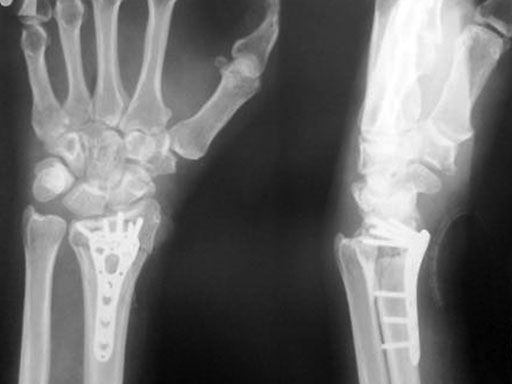

Fig 3ac Postoperative x-rays showing comparison of plate alternatives.